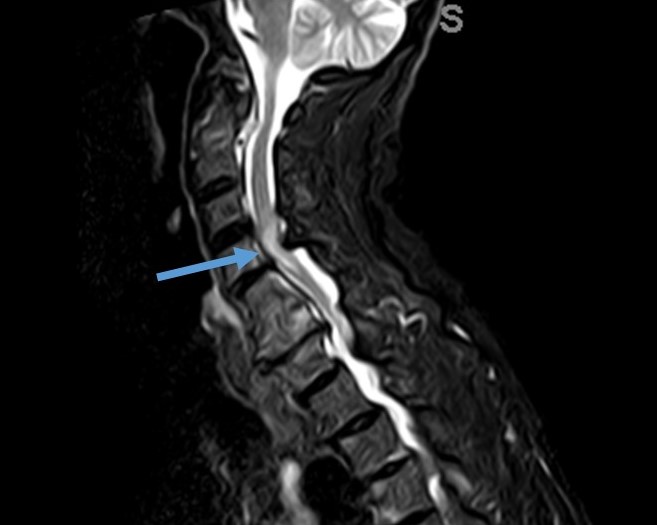

La mielopatía cervical espondiloartrósica está causada por la ocupación central del canal raquídeo por material discal y/o osteofitos (prominencias óseas en los bordes de la vértebras debidas a los fenómenos degenerativos). Esto da lugar a un estrechamiento o estenosis del canal cervical que de forma mantenida comprime e induce un daño en la médula espinal (mielopatía), lo que se traduce en la aparición de torpeza para los movimientos finos en las manos y dificultad para la marcha. Puede dar lugar a la pérdida progresiva de fuerza y sensibilidad en las cuatro extremidades. Todo ello hace que deba valorarse el tratamiento quirúrgico para detener su progresión.